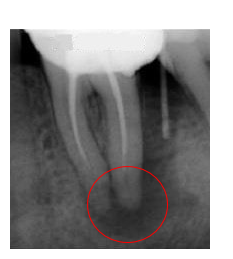

Durante la devitalizzazione , il dentista non fa altro che rimuovere la parte di tessuto, chiamata polpa dentaria, che sta all’interno del dente e lungo tutta la sua radice.

I tessuti di sostegno (osso alveolare, gengiva e legamento parodontale) non vengono interessati dalle procedure di devitalizzazione ma hanno anch’essi la loro vascolarizzazione e la loro innervazione.

In poche parole quando un dente devitalizzato fa ancora male, i responsabili del dolore sono proprio questi tessuti, che infiammati o peggio ancora infettati (nel secondo caso si parla di ascesso dentale), stimolati dalla compressione in masticazione e in occlusione, provocano dolore.

Entrambe le situazioni mantengono una carica batterica residua nei lumi dei canali non trattati che portano nel tempo ai cosiddetti granulomi apicali, forme di infezioni croniche a lenta evoluzione.